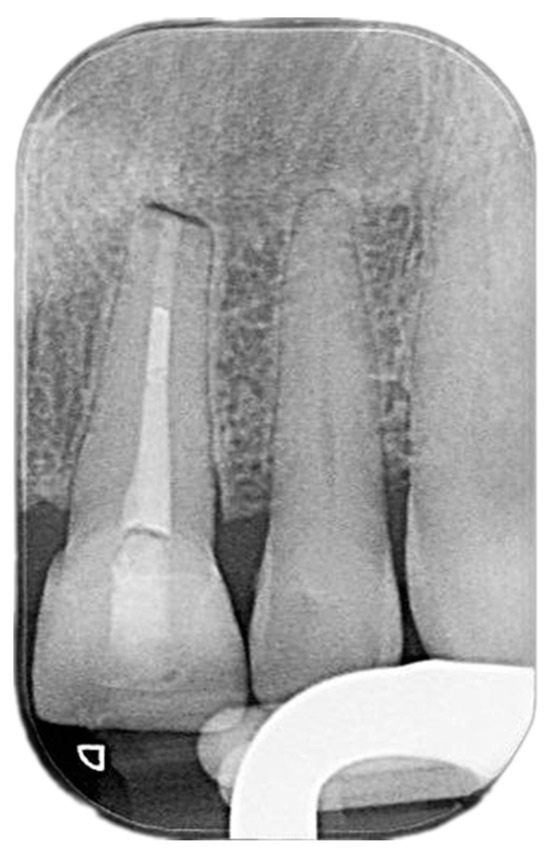

2. Case Presentation

2.2. Delivery of Treatment

2.4. Healing of the Defect and Follow Up